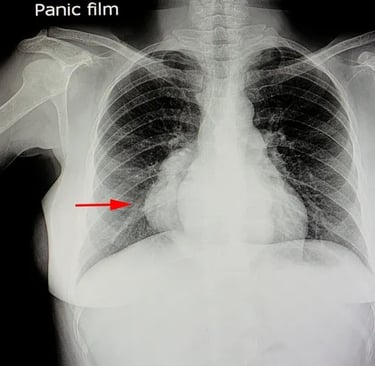

Mediastinal muayene: venöz dolgunluk, SVC sendromu bulguları, stridor/nefes darlığı.

Metabolik olarak aktif tümör dokusunun (florodeoksiglikoz - FDG tutulumu) şeker tüketimini gösteren PET-CT, teşhis algoritmamızın keskin nişancısıdır.

LR+ : ~9.5 (Pozitif bir PET, lenfoma ihtimalini dramatik şekilde artırır).

LR- : ~0.05 (FDG tutulumu yoksa, agresif lenfoma ihtimalini neredeyse sıfıra indiririz).

Kritik Kriter: Deauville Skoru (5 Nokta Skoru):[5] PET tutulumunu mediasten ve karaciğer tutulumu ile karşılaştıran standart bir dildir.

Deauville 1-3: Negatif (Tedaviye yanıt veya reaktif tutulum).

Deauville 4-5: Pozitif (Aktif tümör veya progresyon).